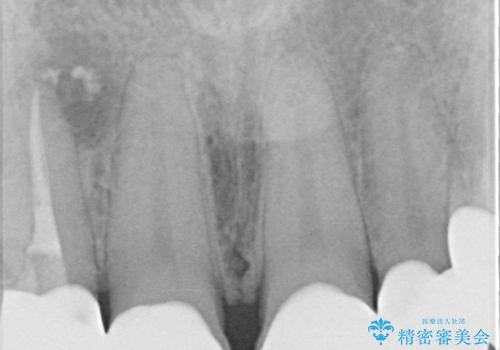

- 患者様は「前歯の見た目をきれいにしたい」というご希望で来院されました。

拝見すると、上顎前歯部にはCR充填(レジン修復)が繰り返し行われており、つぎはぎ状になっていました。そのため、

色調が不自然

形態にばらつきがある

笑ったときに治療跡が目立つ

といった審美的なお悩みが認められました。

また、右上側切歯は根管治療が必要な状態でした。

右上側切歯に対して根管治療を行い、その後右上側切歯から左上犬歯まで計5本をオールセラミッククラウンで補綴する治療計画をご提案しました。